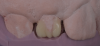

(1.) Pretreatment smile, left lateral smile, and right lateral smile photographs, respectively, showing the patient’s peg-shaped lateral incisors.

Figure 1

(2.) Pretreatment smile, left lateral smile, and right lateral smile photographs, respectively, showing the patient’s peg-shaped lateral incisors.

Figure 2

(3.) Pretreatment smile, left lateral smile, and right lateral smile photographs, respectively, showing the patient’s peg-shaped lateral incisors.

Figure 3

A 16-year-old female patient presented with the chief complaint that she was dissatisfied with the appearance of her anomalous maxillary lateral incisors (teeth Nos. 7 and 10) and multiple diastemas (Figure 1 through Figure 4). She had been referred for restorative treatment after an initial consultation with the orthodontist. Her first restorative appointment was dedicated to data collection, which included a health history and physical examination as well as the acquisition of photographs (facial, dentofacial, dental), videos (chief complaint, F sound, S sound), vinyl polysiloxane (VPS) impressions, a panoramic radiograph, a bite registration, and a facebow registration. The clinical examination revealed that both of the patient's maxillary lateral incisors were peg-shaped. After a discussion about the risks and benefits of different treatment options, such as direct composite restoration, indirect composite veneers, and porcelain laminate veneers, she chose to have her maxillary lateral incisors treated with direct composite buildup restorations. The index cutback technique was chosen for this case instead of a freehand technique in order to create a new shape according to an ideal wax-up but also to be able to control the thickness of the enamel layer.7